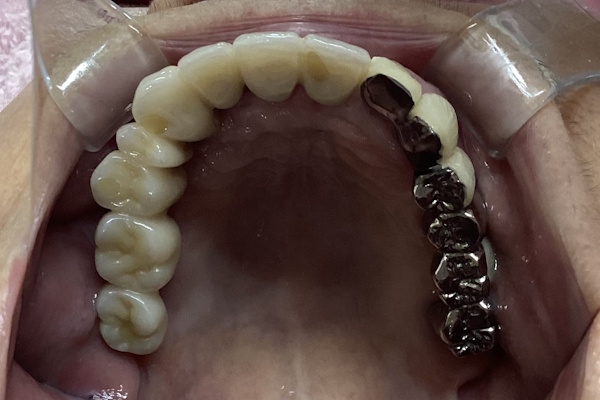

実際の見た目の写真